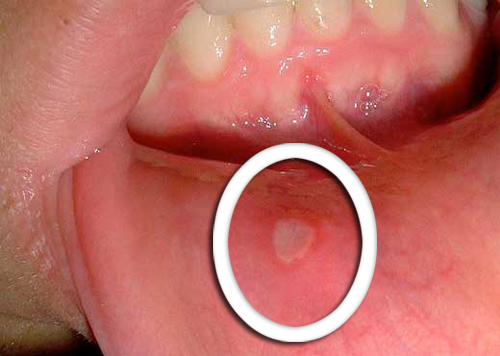

Mudanças físicas na boca

- O sintoma mais inicial do câncer de orofaringe é o desenvolvimento de pequenas feridas que nunca se curam.

- Por outro lado, também é habitual a aparição de manchas vermelhas ou brancas tanto na área da língua, na gengiva ou, inclusive, nos cantos dos lábios.

- É importante estar consciente de que qualquer mudança não habitual que não melhore com o passar dos dias, um médico deve ser consultado.